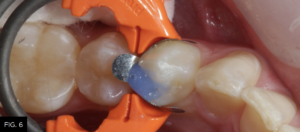

A fifteen second total-etch protocol, 10 seconds on enamel margins and 5 seconds on dentin surfaces is performed using a 37% phosphoric etchant.

(FIG. 6)

Total-etch with 37% phosphoric acid (Max Etch, Clinician’s Choice) is performed for 15 seconds, then completely rinsed with water. Any excess remaining moisture is removed with the high-volume suction device (not the air syringe!) to avoid over desiccation and collapse of exposed collagen, which could lower the bond strength of the adhesive to the dentin.